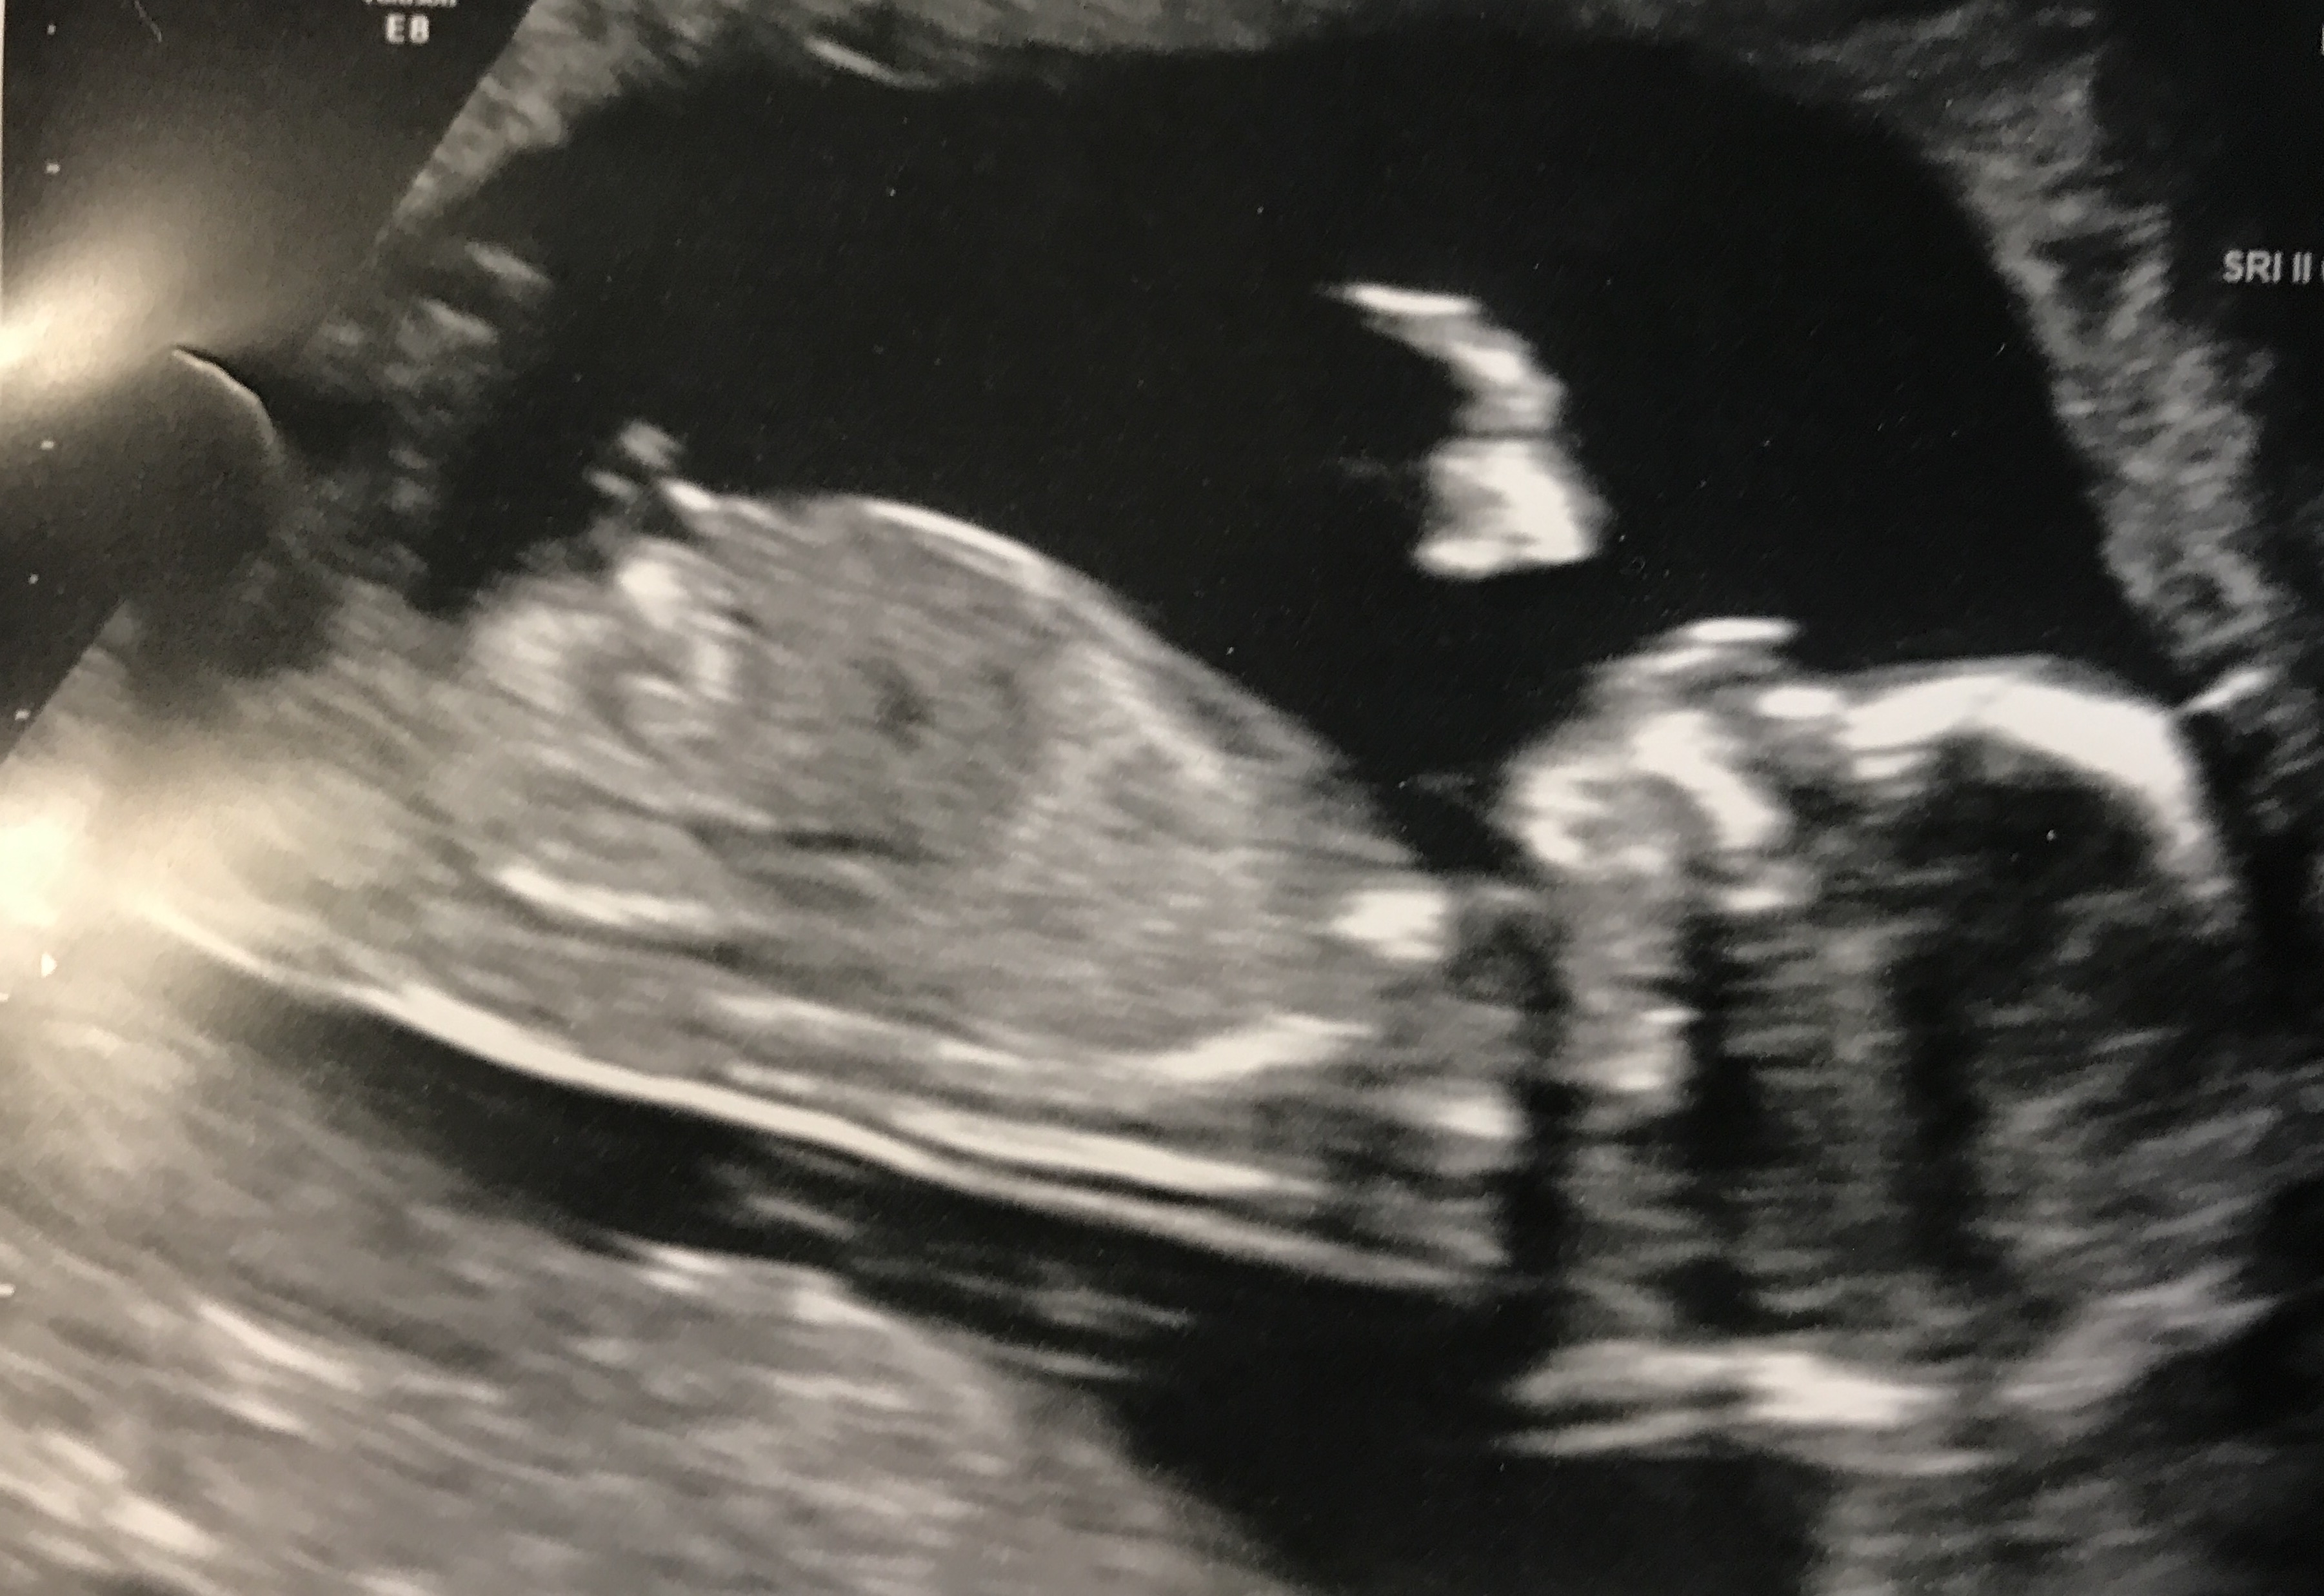

Nub Guess - 13 weeks 2 days

I would guess girl.